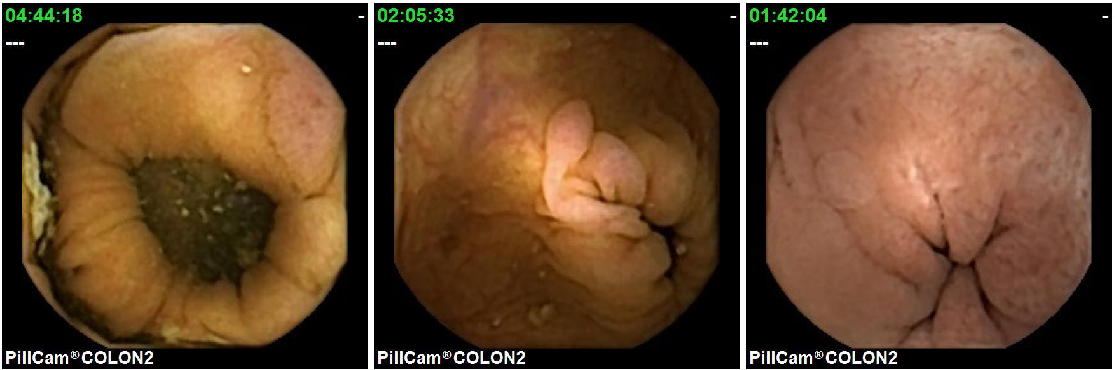

With regard to the specific goal of polyp detection, most of the published systems have been reported and validated as automatic detection methods. However, because of legal and practical reasons, these systems cannot be used for automatic diagnosis and can only be deployed as decision support systems which filter the whole set of frames to allocate physician’s attention to those images that show potential polyp structures. In most cases, this is a needle-in-haystack problem because of the occasional appearance of images with these pathologies. Figure 1 shows two sequences from different procedures where a polyp is observed. It is important to point out that, in both procedures, those are the only images of the whole procedure where a polyp is visible. Figure 2 shows some random images from the same procedures.

The second important point to consider when creating the database and its evaluation methodology, is that although all polyps have common visual characteristics, the appearance of different polyps from the same patient must be considered. The first row of Figure 5 shows three different polyps from the same patient, while the second row shows three polyps from different patients. As it can be observed, those polyps from the same patient are generally similar in shape and texture while the polyps from other patients are more diverse. It is for this reason, that training and test set must not use images from the same procedures.

Figure 6 shows 9 polyp samples of different sizes and morphologies.